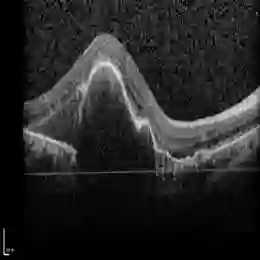

Current methods for multimodal medical imaging based disease recognition face two major challenges. First, the prevailing "fusion after unimodal image embedding" paradigm cannot fully leverage the complementary and correlated information in the multimodal data. Second, the scarcity of labeled multimodal medical images, coupled with their significant domain shift from natural images, hinders the use of cutting-edge Vision Foundation Models (VFMs) for medical image embedding. To jointly address the challenges, we propose a novel Early Intervention (EI) framework. Treating one modality as target and the rest as reference, EI harnesses high-level semantic tokens from the reference as intervention tokens to steer the target modality's embedding process at an early stage. Furthermore, we introduce Mixture of Low-varied-Ranks Adaptation (MoR), a parameter-efficient fine-tuning method that employs a set of low-rank adapters with varied ranks and a weight-relaxed router for VFM adaptation. Extensive experiments on three public datasets for retinal disease, skin lesion, and keen anomaly classification verify the effectiveness of the proposed method against a number of competitive baselines.

翻译:当前基于多模态医学成像的疾病识别方法面临两大挑战。首先,主流的“单模态图像嵌入后融合”范式无法充分利用多模态数据中的互补与关联信息。其次,标注多模态医学图像的稀缺性,加之其与自然图像存在显著的领域偏移,阻碍了前沿视觉基础模型(VFMs)在医学图像嵌入中的应用。为协同应对这些挑战,我们提出了一种新颖的早期干预(EI)框架。该框架将一种模态视作目标模态,其余作为参考模态,利用参考模态的高层语义标记作为干预标记,在早期阶段引导目标模态的嵌入过程。此外,我们引入了混合低变秩自适应(MoR),这是一种参数高效的微调方法,它采用一组具有不同秩的低秩适配器和一个权重松弛路由器来实现对VFM的自适应。在视网膜疾病、皮肤病变及膝关节异常分类三个公开数据集上进行的大量实验验证了所提方法相对于多个竞争基线的有效性。